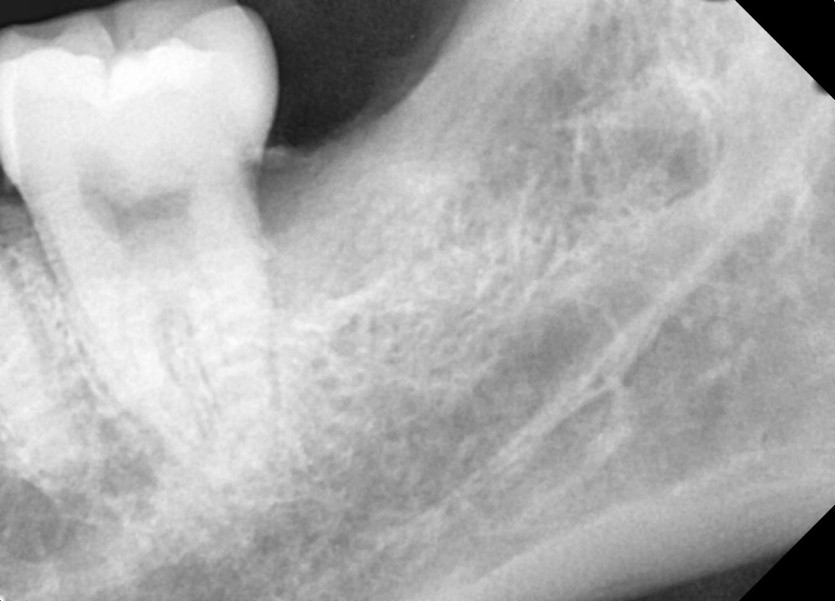

#28,38 사랑니 발치

구강 외과 전문의가 당일 발치했습니다.